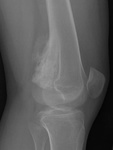

Да, надо отметить, что "это" прекрасно видно на рентгенограммах. Вопрос к автору ветки - кто направил пациента на МРТ и с каким диагнозом?

Окончательное мнение - костно-хрящевой экзостоз. Прилагаю РКТ коленного сустава (пациент не тот, что на МРТ)

О! Это понятно: экзостозы (2), остеофиты, очаги окостенения в мягких тканях.

Давайте разберемся, уважаемые коллеги, что в данном случае понимаем под термином "экзостоз": 1. опухоль - остеохондрому (костно-хрящевой экзостоз), остеому; 2. дегенеративно-дистрофические изменения (остеофиты, оссификаты в точке прикрепления сухожилий и т.д.). Внутрисуставной хондроматоз к "экзостозам" отношения не имеет

Если в демонстрации предполагается костно-хрящевой экзостоз, т.е. остеохондрома, то:

"Строение остеохондромы весьма характерно. Опухоль имеет грибовидную форму, ее размеры варьируют в пределах 1—20 см. Наружный слой головки этого новообразования покрыт различной толщины доброкачественным гиалиновым хрящом, хорошо видимым при МРТ. Хрящ имеет вид дезорганизованной ростовой пластинки. Он подвергается энхондральной оссификации, а вновь образованная кость формируется во внутренних частях головки и ножки. Корковый слой ножки опухоли сливается с аналогичным слоем диафиза кости, а костномозговые полости остеохондромы и самой кости сообщаются между собой."

Выделенная шрифтом фраза это ключевые отличительные дифференциально-диагностические признаки костно-хрящевого экзостоза от других поверхностных костных образований.

За надколенником по передней поверхности бедренной кости на МРТ и РКТ (наверное не так наглядно) - костно-хрящевой экзостоз.

+ на РКТ проекционно на уровне средней трети диафиза бедренной кости кпереди от нее - фокусы хондроматоза.

Уважаемый коллега, nnemo, большое спасибо, за уточнение, что Вы подразумеваете именно костно-хрящевой экзостоз, т.е остеохондрому. Где Вы его подразумеваете я, вобщем-то, догадалась. Однако, я спрашивала и просила показать на МРТ: на основании каких семиотических признаков Вы сделали заключение, что это именно остеохондрома, а не какая-то другая патология?

tatyana, Вы в чем то правы. Складывается впечатление что кортикальная пластинка бедренной кости почти не изменена (или не изменена вовсе). Поэтому и были сомнения. Кроме того можно отметить, что вся синовиальная оболочка бурсы тотально утолщена, что тоже наводила на определенные соменения. Наверное изменение кортикальной пластинки, которые абсолютно четко увяжут заключение с костно-хрящевым экзостозом, можно указать с "натяжкой". Скорее это волевое решение в пользу костно-хрящевого экзостоза. Еще были мнения "вилонодулярном синовиите", а также "хондроматозе". Так что возможны варианты.

Пока скажу, что пациент недообследован. ;) + не нравиться качество снимка. По данному снимку можно думать о чем угодно. Можно еще несколько рентгенограмм его же?

Вы хочете снимков? их есть у меня ))) Даже в качестве бонуса томограммки ;)))

Да, кстати, по этим снимкам было дано заключение, затем полностью подтвержденное морфологически

Похоже, что не в самой кости.

Т.е. не из кости, Валентин Львович?

Чевой то мне, паростальную напоминает.

Неужели не похоже на экзостоз?!

Преклоняюсь перед людьми, которые по таким рентгенграммам выставляют точный морфологический диагноз. Это практически режим Бога (God mode), как говорят в компьютерных играх. Тенденцию к комплексу неполноценности можно развить в ком угодно (и Вам это почти удалось). По моему "это" широко прилежит или даже правильнее сказать исходит из кости. При этом несколько утолщая кортикальную пластинку и суживая костно-мозговой канал на этом уровне. Если заключение лежит в плоскости текущего поста, то я бы больше склонился к костно-хрящевому экзостозу, хотя тут диф ряд может проистекать от оссифицированной гематомы до неопроцесса.

P.S. Я показала паростальную остеосаркому, как сходу и написал Валентин Львович ))))